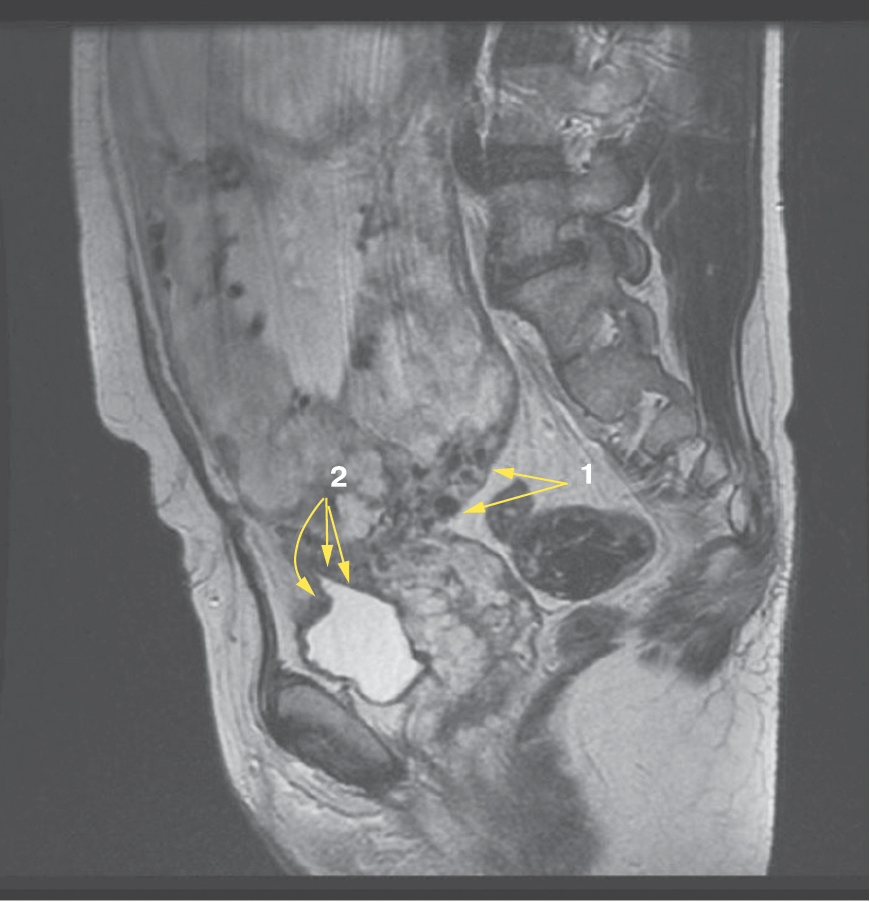

Является ли симптом «обнаженного сосуда» патогномоничным для параметральной инвазии или нет, еще предстоит выяснить; однако в ходе исследования установлена его связь с частотой гистерэктомий в группах с наличием симптома «обнаженного сосуда», что, вероятно, обусловлено мощной сосудистой сетью коллатералей и неоангиогенезом. Во всех случаях обнаружения данного признака впоследствии была выполнена вынужденная гистерэктомия (рис. 3–6, пациентка Н., 37 лет).

Рис. 5. Корональная проекция МРТ. 1 – интрамуральная гиперваскуляризация; 2- измененный контур мочевого пузыря

Рис. 6. Корональная проекция МРТ. 1 – обнаженный сосуд; 2 – интрамуральная гиперваскуляризация; 3 – гиперваскуляризация плаценты